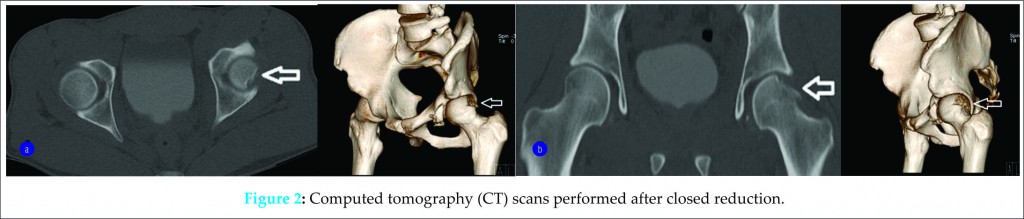

Closed reduction was performed successfully in the emergency department. Radiographs and CT scans identified a 25 x 10-mm osteochondral defect of the posterosuperior quadrant of the femoral head near the head-neck junction with an impaction depth of 5 mm. In addition, a small, comminuted, minimally displaced anterior acetabular wall fracture was also identified but was not amenable to fixation (Figures 1A-1B and 2).